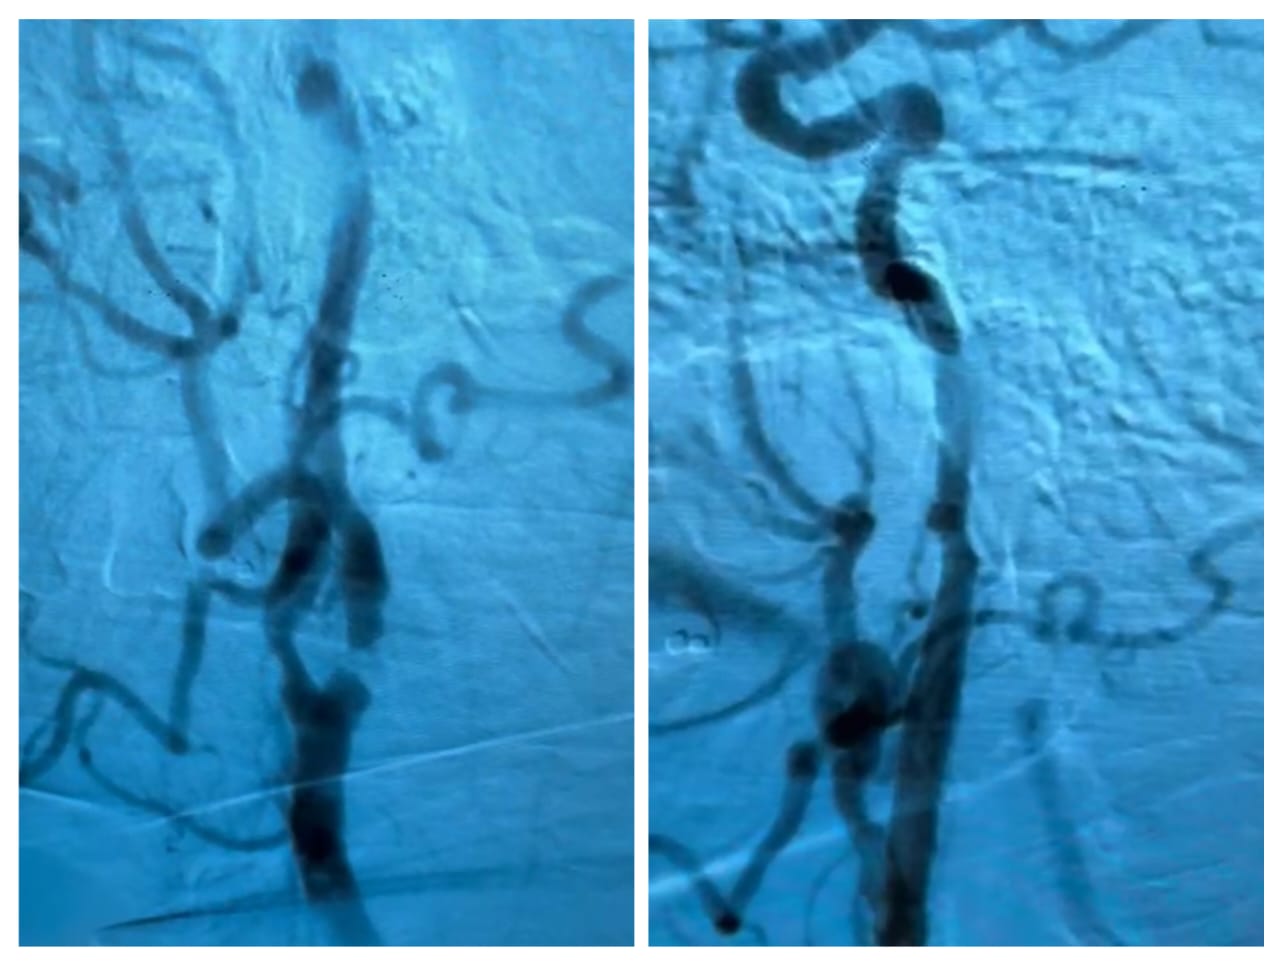

No dia 24 de junho de 2025, o Hospital Universitário Maria Aparecida Pedrossian da Universidade Federal de Mato Grosso do Sul (Humap-UFMS), vinculado à Rede Ebserh, realizou sua primeira angioplastia de carótidas, marcando um avanço significativo na prevenção e tratamento do Acidente Vascular Cerebral (AVC) isquêmico. O procedimento foi conduzido pela equipe da cirurgia vascular, na sala de Hemodinâmica, com o apoio de uma equipe multiprofissional.

A angioplastia de carótida é uma técnica minimamente invasiva que utiliza um cateter inserido por via endovascular — geralmente por punção na artéria femoral — para acessar a artéria carótida. Nela, é inserido um stent que restaura o fluxo sanguíneo adequado, reduzindo o risco de AVC ao impedir que placas de gordura instáveis causem obstruções ou embolias cerebrais.